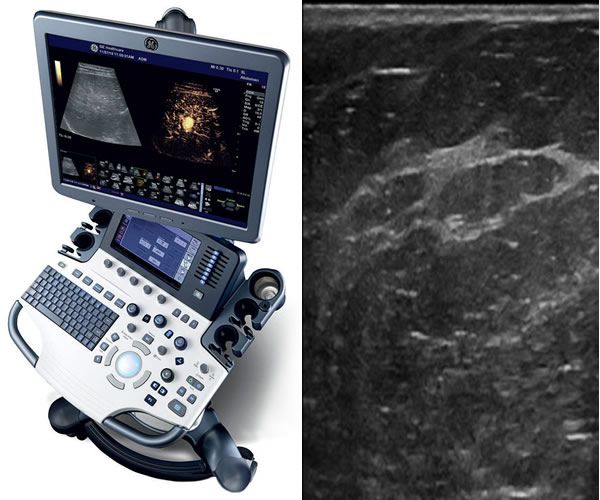

Masse maligne absorbante

Masse ACR5 de contours irréguliers

- ACR 5 : L'anomalie est évocatrice d'un cancer.